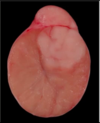

Neoplasia

A

- Seminoma

- Sertoli cell tumor

- Interstitial cell tumor

- Teratoma

- just like teratoma in ovary (2 germ cell layers)

11

Q

A

- Interstitial cell tumor

- most common testicular tumor in dogs, cats, bulls

- almost always benign

- can produce estrogen

- Gross Morph typically

- spherical

- well demarcated

- tan to orange

- possible hemorrhages

- generally firm-ish